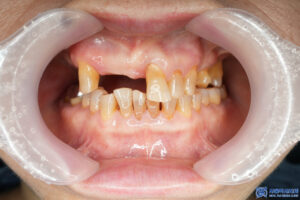

위 환자분께서는 예전에 다른 치과에서

신경치료를 받았던 치아가 너무 아프다며

서울박사치과를 찾아주셨습니다.

아픔을 참다 참다 결국 치아를

빼달라고 하실 정도로 통증이 심하셨는데요.

파노라마 X-ray를 촬영해보니 문제가

확연히 드러났습니다.

과거에 신경치료를 받았던 치아가

뿌리까지 파절되어 있었는데요.

치아가 파절되면 음식물을 씹을 때마다

큰 통증이 생길 수밖에 없고,

신경치료로는 더 이상 회복이 불가능하기 때문에

발치 후 임플란트를 진행해야 합니다.